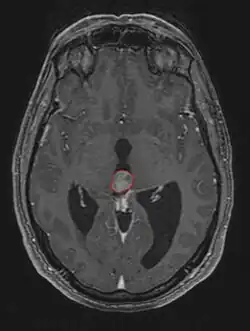

Radiation Oncology/CNS/Pineal

Pineal Gland Tumors

Clinical Presentation

• Determined by the spatial anatomy and direction of growth

• Obstruction of aquaduct: hydrocephalus presenting as headaches, nausea, vomiting

• Compromise of superior colliculus: vertical gaze palsy, pupillary and oculomotor nerve paresis (Parinaud syndrome)

• Work-up includes MRI, CSF, serum markers for bHCG and AFP

• Tissue diagnosis is critical, since management varies significantly based on pathology